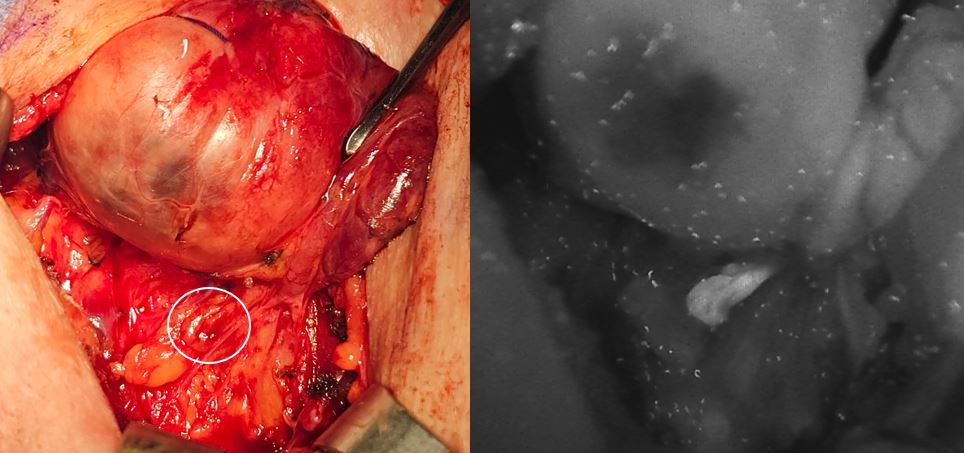

Σημείωση: Τα αδενώματα παραθυρεοειδούς σπάνια εκπέμπουν αυτόφθορισμο, άρα δεν εντοπίζονται πάντα με την ειδική κάμερα.

parathyroid camera

Εντοπισμός παραθυρεοειδούς αδένα και σιγουρη επιβεβαιωση με τη χρήση της ειδικής κάμερας παραθυρεοειδών